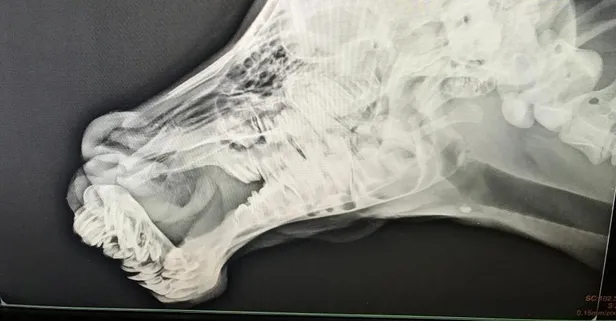

Yapılan incelemede buzağıda ikinci bir çene yapısı ve dil şekillendiği görüldü. Tarım ve Orman Bakanı Bekir Pakdemirli'nin talimatları ile buzağı Diyarbakır Dicle Üniversitesi Veteriner Fakültesi cerrahi kliniğinde getirilerek tedavi altına alındı.

İşte buzağının operasyondan önceki hali: